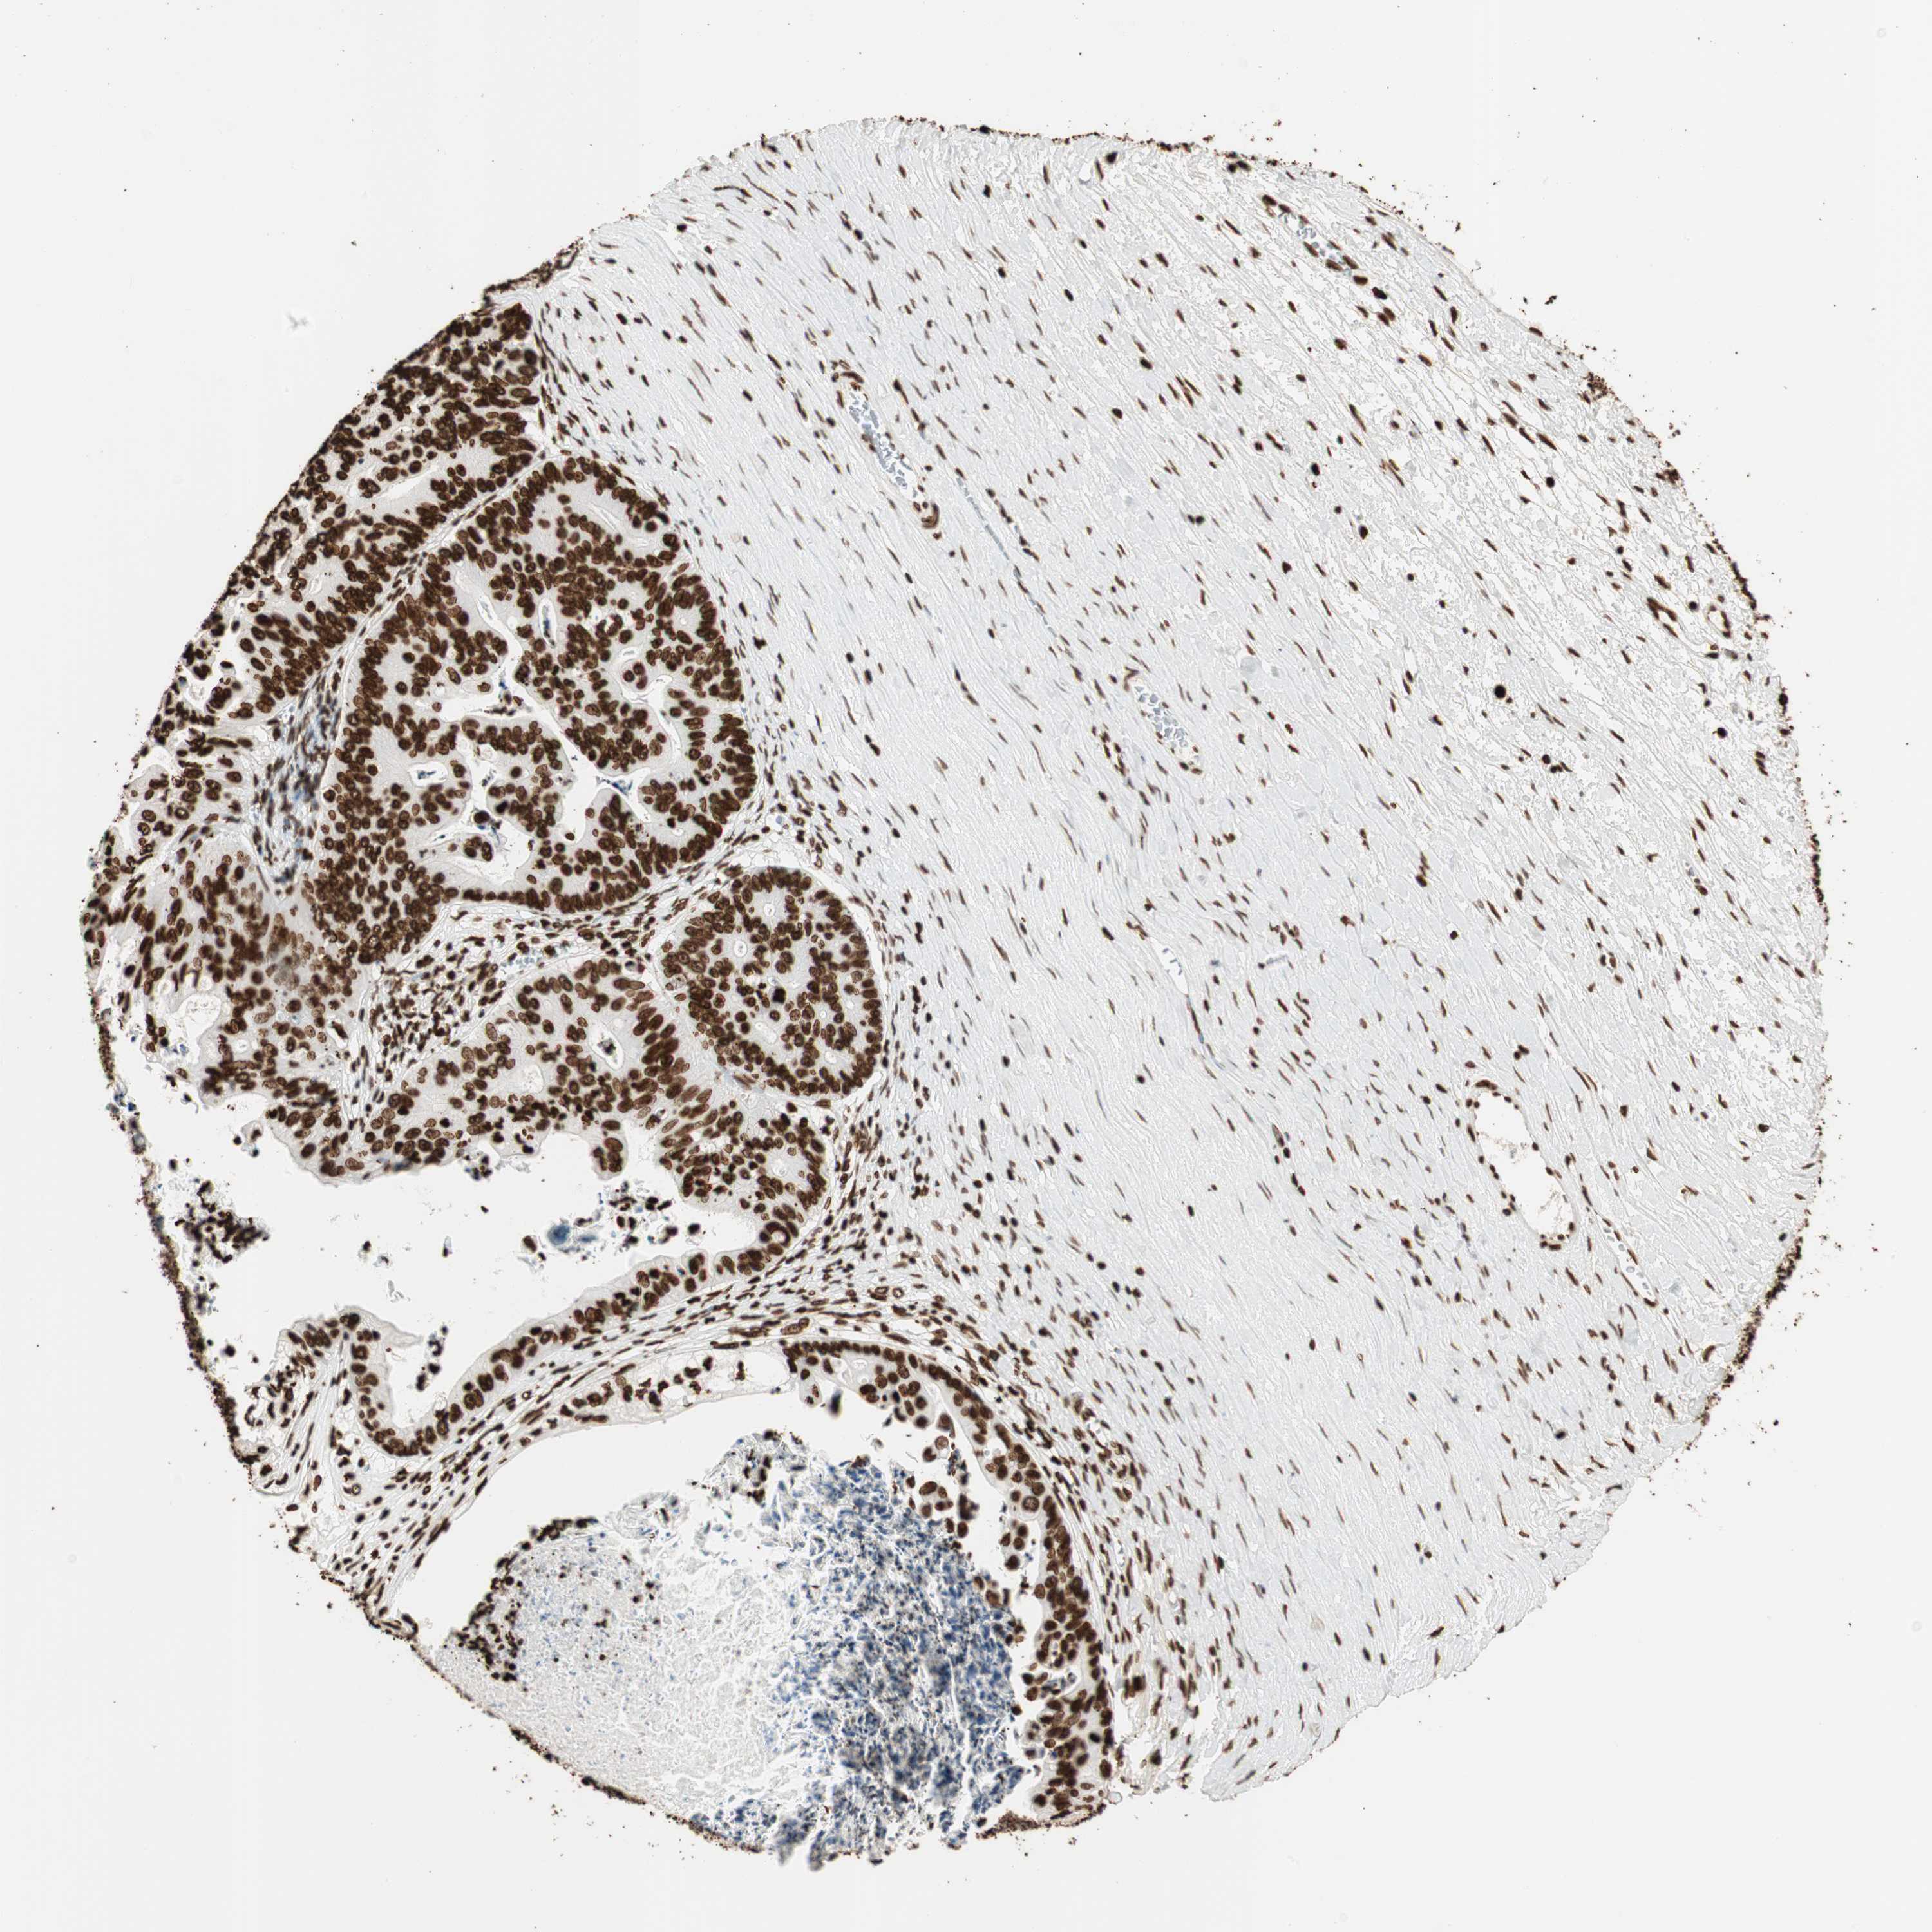

OVARIAN CANCER - Protein expressioni

A mouse-over function shows sample information and annotation data. Click on an image to view it in a full screen mode. Samples can be filtered based on level of antibody staining by selecting one or several of the following categories: high, medium, low and not detected. The assay and annotation is described here.

Note that samples used for immunohistochemistry by the Human Protein Atlas do not correspond to samples in the TCGA dataset.

Antibody stainingi

Antibody staining in the annotated cell types in the current human tissue is reported as not detected, low, medium, or high, based on conventional immunohistochemistry profiling in selected tissues. This score is based on the combination of the staining intensity and fraction of stained cells.

Each image is clickable and will lead to virtual microscopy that enables deeper exploration of all samples and also displays staining intensity scores, fraction scores and subcellular localization as well as patient and tissue information for each sample.

Antibody CAB008558

Staining

High

Medium

Low

Not detected

Intensity

Strong

Moderate

Weak

Negative

Quantity

>75%

75%-25%

<25%

None

Location

Nuclear

Cytoplasmic/membranous

Cytoplasmic/membranous,nuclear

Cystadenocarcinoma, serous, NOS

Carcinoma, endometroid

Cystadenocarcinoma, mucinous, NOS

Carcinoma, NOS